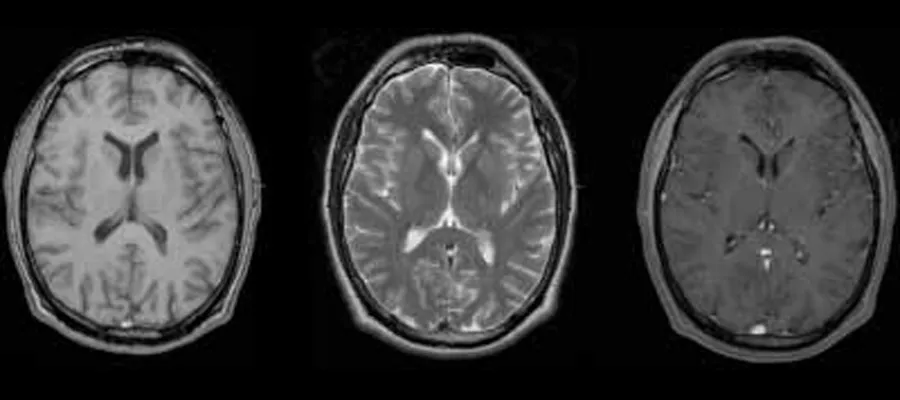

magnetic resonance image of the brain

In work partly funded by the RS MacDonald Charitable Trust, three patients were identified demonstrating a highly stereotyped clinical and radiological phenotype comprising initially normal development, followed by the onset of epilepsy and a loss of skills in the second year of life, and then death by age 3 years. Study of the brain of one child revealed features consistent with a mouse model of NRROS deficiency, and transcriptomic analyses showed that brain expression of NRROS is highly localised to microglia in humans and mice. These findings indicate that NRROS is indispensable in controlling the early development of a homeostatic microglial population, and/or its ongoing preservation in the postnatal brain, and define a loss of NRROS function as a novel microgliopathy in humans. Further studies to explore the cellular pathology underlying with this fatal encephalopathy are warranted.